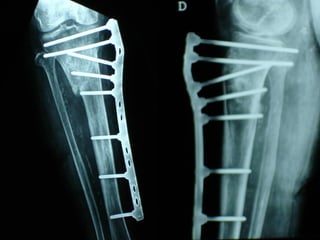

MIPPO

Dal Gennaio 2000 al Febbraio 2006 abbiamo trattato 167 fratture chiuse  con placca percutanea  in 164 pazienti :  27 lesioni diafisarie di gamba, 12 piloni tibiali ,  11 fratture prossimali di tibia, 36 fratture sovracondiloidee di femore, 17 fratture diafisarie di femore, 43 fratture metaepifisarie prossimali di omero, 21 diafisarie d’omero.  156 guarigioni 8 fallimenti

I buoni risultati ottenuti dipendono da 5 punti fondamentali:   una accurata riduzione percutanea della frattura  precise vie di accesso  l’utilizzo della placca che consenta il più lungo braccio di leva possibile il pretensionamento della placca  una sintesi con un ridotto numero di viti

Precise vie di accesso

Placche lunghe e pretensionate

Placche lunghe e pretensionate Sintesi con un ridotto numero di viti

VANTAGGI CHIRURGIA MININVASIVA Mini Open Inserimento della placca sottocutaneo per scivolamento Viti percutanee Preservazione dei tessuti molli Ridotto danno vascolare Rapida ripresa funzionale